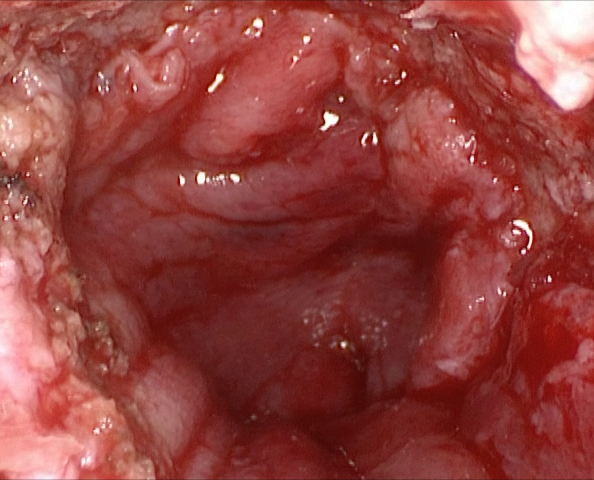

Introducción: La cirugía endoscópica endonasal se ha convertido en una herramienta fundamental para el manejo de patologías que comprometen la base de cráneo. En casos bien seleccionados, estas técnicas permiten resecciones quirúrgicas con una menor morbilidad sin comprometer los principios oncológicos de resección. Con el desarrollo de instrumental especializado, nuevas tecnologías y la experiencia de los cirujanos, la cirugía endoscópica endonasal se usa cada vez más en cirugía de base de cráneo en niños.

Resultados: Fueron intervenidos 8 pacientes entre los 2 y 14 años, con una edad promedio de nueve años y un seguimiento promedio de 16 meses. En el 75% se hizo una resección total del tumor. Un paciente requirió una reintervención y un paciente fue sometido a radiocirugía post-operatoria. 1 paciente falleció a pesar de múltiples intervenciones, quimioterapia y radioterapia.

Conclusión: La cirugía endoscópica endonasal para tumores de base de cráneo puede ser utilizada de forma segura en los pacientes pediátricos, es una técnica que en casos bien seleccionados pueden ofrecer excelentes resultados disminuyendo la morbilidad y complicaciones de las técnicas abiertas.